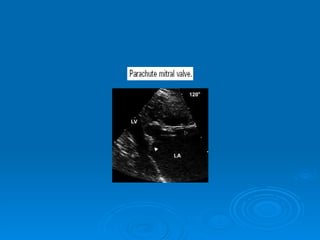

Echo-doppler Cardiaque Echographie bidimentionnelle: Épaississement de la valve Diminution d’ouverture valvulaire Aspect caractéristique en genou fléchi de la GVM Mesure de la surface mitrale Recherche de calcifications Recherche de thrombis intra auriculaire gauche Dilatation de OG Etude de l’appareil sous valvulaire

Echo-doppler Cardiaque Echographiebidimentionnelle: Épaississement de la valve Diminution d’ouverture valvulaire Aspect caractéristique en genou fléchi de la GVM Mesure de la surface mitrale Recherche de calcifications Recherche de thrombis intra auriculaire gauche Dilatation de OG Etude de l’appareil sous valvulaire